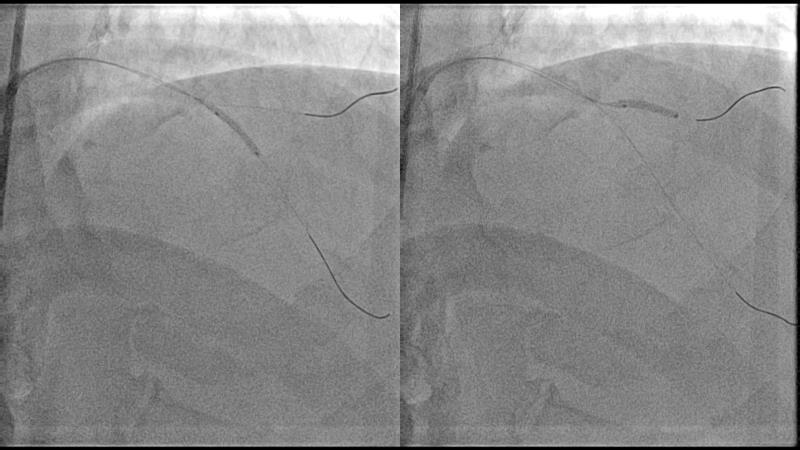

With this session, keep up to date on the evidence, trials and outcome data for intravascular lithotripsy in severely calcified lesions. Learn how to use this technique in real-world patients and understand its role in the treatment algorithm for severely calcified coronary lesions.

- To learn how to use intravascular lithotripsy in real-world patients with severely calcified coronary lesions